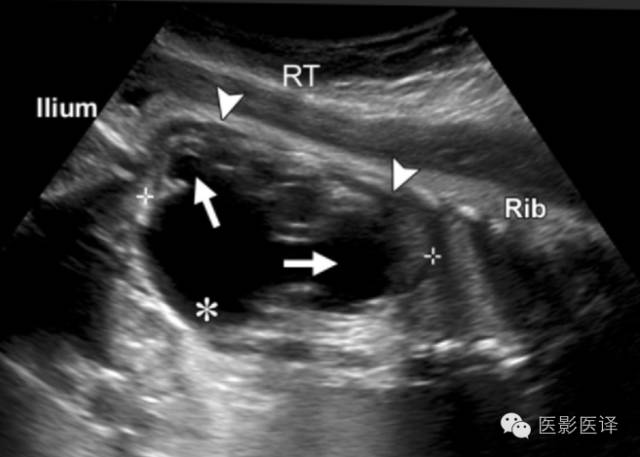

超声检查中,复杂性卵巢囊肿是厚壁的,且回声不均质。图像特征包括多个分隔(图4、5)、内部移动性高回声、实性表现(图6),或液液平面(图5、7)。复杂性囊肿被认为是扭转的结果,胎儿比新生儿更常发生。出现复杂性囊肿的表现高度提示需要手术。与胎儿卵巢囊肿伴发的其他影像表现包括羊水过多和腹水,可能是由于漏出或囊肿破裂所致。肠管或肾脏的继发梗阻被认为是扭转时卵巢坏死引起的粘连所致。

图7 囊肿中的液液平面。(a)轴位胎儿超声图像显示在左肾(LK)前方一个孤立性囊性肿块(箭),脊柱(Sp)另一侧可以看到正常的右肾(RK),三周后的随访图像(未展示)显示团块中出现液液平面。(b)新生儿经腹长轴位图像显示一个薄壁囊性团块,有液液平面(箭),子囊(箭头)是卵巢囊肿的确诊征象。(c)新生儿矢状位T2WI显示一个出血性卵巢囊肿,有液液平面(箭)和低信号血液成分。